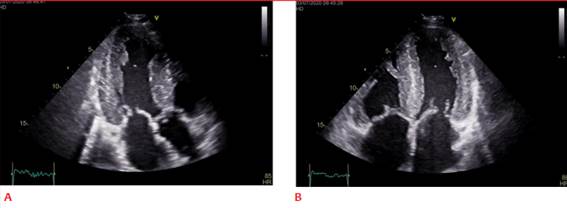

El principal cambio morfológico objetivable es el aumento del espesor parietal de VI mayor a 12 mm en ausencia de causas que lo expliquen8. Se considera criterio diagnóstico de compromiso cardíaco en los casos donde contamos con el diagnóstico confirmado de amiloidosis sistémica8 (figuras 1A y 1B). La presencia de hipertrofia ventricular asociada a hallazgos electrocardiográficos compatibles como microvoltaje, trastorno de conducción intraventricular y pseudoonda q aumentan la sospecha clínica de AC, pero el diagnóstico diferencial con otras causas de hipertrofia no se puede descartar9.

Figura 1: A. Vista apical de 3 cámaras. Hipertrofia con severo aumento de espesor parietal y patrón especulado del miocardio. B. Vista apical de 4 cámaras. Se aprecia aumento del espesor del septum interauricular y de los velos mitral y tricúspideos e hipertrofia de VD.

La presencia de un aspecto granular o espiculado del miocardio ventricular ha sido descrita como elemento sugestivo de compromiso amiloidótico (figuras 1A y 1B). Esta puede ser difusa o localizada en segmentos específicos y se debe a que las proteínas que conforman el amiloide son más ecogénicas que el miocardio10. Los segmentos más frecuentemente involucrados son el septum y la pared posterior, respetando el ápex. Esta distribución refleja el patrón de depósito de amiloide a nivel de miocardio11. Si bien es un signo orientador, no es un signo característico, puesto que puede observarse en otros tipos de cardiopatías que cursan con hipertrofia, así como en la enfermedad renal crónica avanzada7. Cabe aclarar que es un signo ecocardiográfico descrito para la evaluación con imagen fundamental, ya que la imagen armónica puede generar un aspecto espiculado, elemento que baja aún más la especificidad de este signo.

Otras características morfológicas sugestivas de compromiso infiltrativo es la presencia de volúmenes ventriculares pequeños con FEVI conservada y bajo volumen latido, auriculomegalia bilateral con disfunción auricular, estasis y eventualmente trombo auricular o en orejuela auricular aún en ritmo sinusal, hipertrofia de ventrículo derecho (VD), engrosamiento valvar (figura 1B), hipertrofia del septum interauricular (SIA) (figura 1B), derrame pleural y pericárdico6,7.